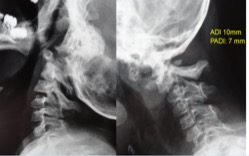

- Figura 1. Radiografias preoperatorias AP y Laterales